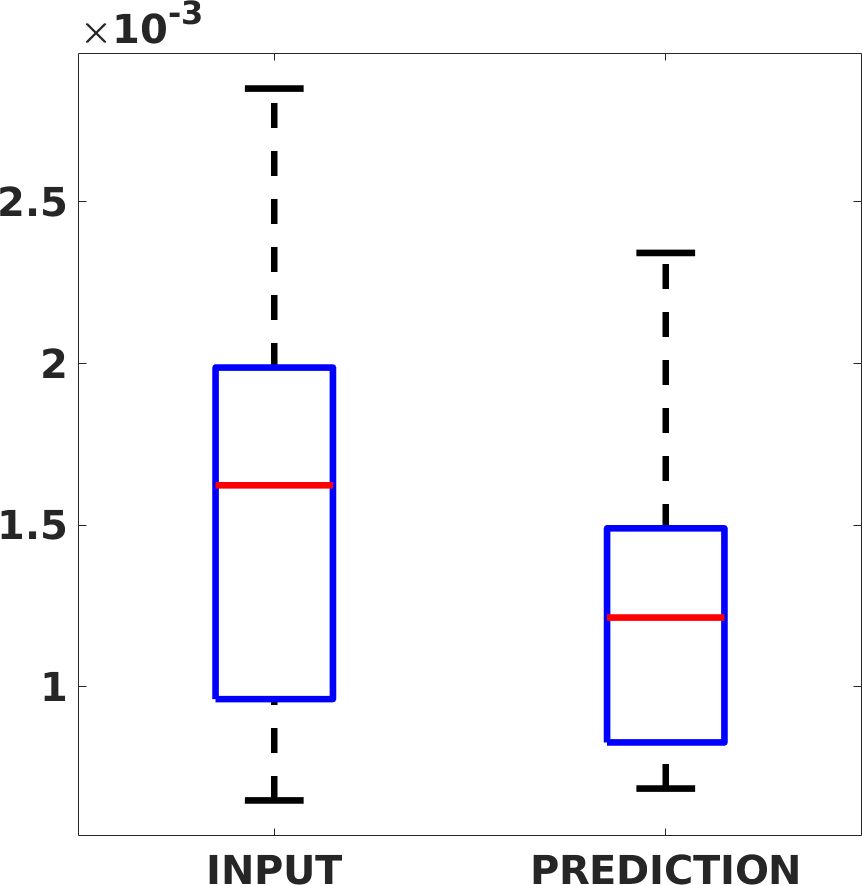

Fig. 7(a-b-c, left) shows the box plot of the statistics of the PSNR on three different anatomical districts, comparing the target images with the prediction and the cubic convolution, respectively. The metrics are computed on a data set of 200 images of the same district and with the same up-sampling factor. We report that the PSNR median value improves of on obstetric 2X raw images, on cardiac 2X raw images, and on abdominal raw 4X images.

Fig. 7(a-b-c, right) shows the histogram of the absolute value of the error with respect to the target image, of the prediction and Cubic convolution results, respectively. The histograms show the number of pixels where the prediction error is lower than 5 (i.e., the first bin of the histogram), which means very similar to the target when visually analysing the images. From the Cubic convolution to the predicted images, this value increases of on obstetric 4X raw images, on cardiac 4X raw images, and on abdominal 4X raw images.

Fig. 8 shows the box plot of the SSIM (a-b-c, left) and MAE (a-b-c, right) quantitative metrics, as performed for PSNR metric. Also, these metrics show that our method improves the results of Cubic convolution both in terms of average value and variability. For example, the SSIM median value improves of on obstetric 4X images and the MAE median value improves of on cardiac 2X images.